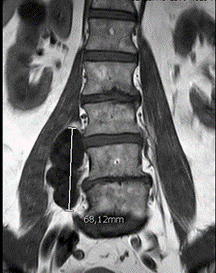

A pelvis MRI confirmed a multilobulated mass involving the right paravertebral muscles in the lower lumbar and sacral region that appeared hypodense on T1-weighted sequences and hyperdense in T2-weighted sequences (Figures 3 & 4).

Figure 3: Coronal MR image of lumbosacral spine show hypointense paravertebral lesion (T1 signal).